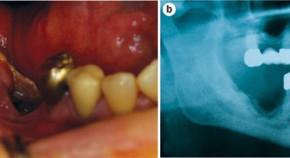

• Osteonecrosis of the jaw (ONJ) is associated with high-dose bisphosphonate therapy in patients with cancer, and has also been linked to bisphosphonate use in patients with osteoporosis. In this Review, the authors examine the epidemiology and pathogenesis of ONJ.

• Ian R. Reid

• Jillian Cornish

Review Article